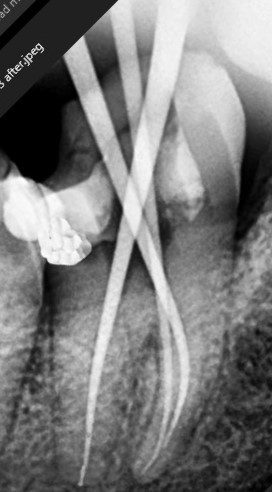

After

Lower Molar

Severe Infection

Lower Molar Root Canal

Infection in the lower molar causing intense pain and swelling. Root canal treatment was performed to save the tooth.

Severe infection eliminated

Pain relief within 24 hours

Natural tooth saved